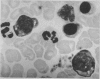

Serial measurements in alcoholic subjects showed a profound fall of serum iron for three days after withdrawal of alcohol and a reversion of abnormal accumulation of erythroblastic haemosiderin to normal. These findings suggest an interference in normal haem synthesis, most probably by a direct effect.